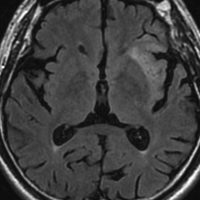

グレード2のオリゴ 乏突起膠腫

平均的な増大速度を示した乏突起膠腫グレード2です。左が無症状で発見された時,右が3年後で,ごくわずかに増大しています。開頭手術で摘出しました。